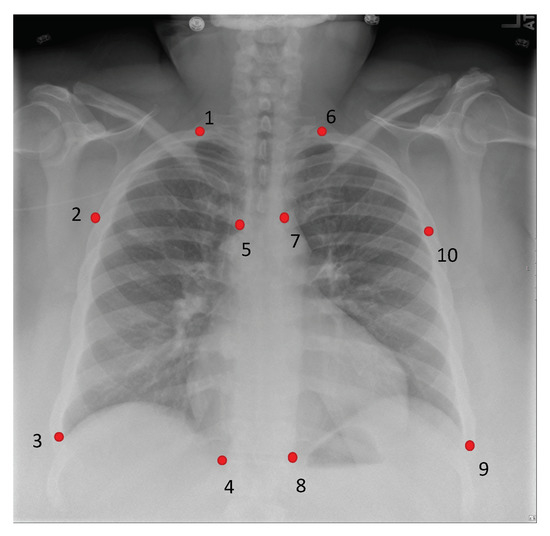

3.1. Portable Radiograph Alignment

| P1 | 27.995/0.970 | 28.780/3.338 | 0.675/0.195 | 0.723/0.086 |

| P2 | 28.079/1.126 | 29.911/2.783 | 0.756/0.065 | 0.763/0.062 |

| P3 | 28.196/1.290 | 30.025/3.031 | 0.669/0.187 | 0.736/0.101 |

| P4 | 27.960/0.672 | 30.519/2.453 | 0.706/0.076 | 0.795/0.051 |

| P5 | 27.898/0.538 | 29.007/2.444 | 0.683/0.077 | 0.736/0.084 |

| P6 | 28.159/1.097 | 28.523/3.328 | 0.699/0.153 | 0.720/0.098 |

| P7 | 28.407/1.143 | 29.576/2.354 | 0.733/0.070 | 0.778/0.059 |

| P8 | 28.595/1.786 | 31.005/2.201 | 0.776/0.063 | 0.802/0.052 |

| P9 | 28.075/0.826 | 30.485/3.503 | 0.721/0.079 | 0.737/0.134 |

| P10 | 27.940/0.676 | 30.738/2.589 | 0.713/0.070 | 0.767/0.067 |